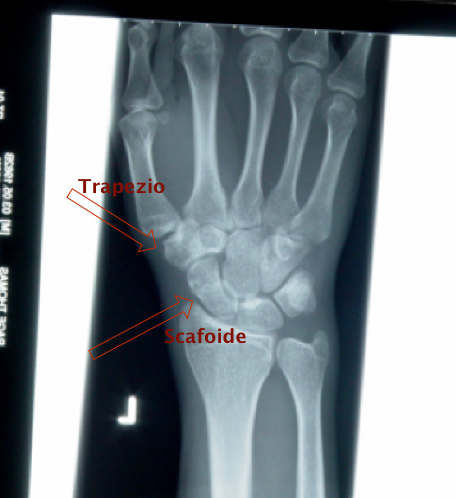

Ok, antenne alzate e ben dritte, ora vi spiego perchè. All’interno del polso ci sono, in pochissimo spazio, 8 “piccoli ossicini” che ci permettono di eseguire la miriade di movimenti che compiono le nostre mani; ognuno di loro si muove in maniera ben precisa rispetto a tutti gli altri anche grazie ai moltissimi piccoli legamenti che tengono unito questo complesso. Ecco, tra questi ci sono lo SCAFOIDE e il TRAPEZIO.

Lo scafoide è uno dei più birichini di tutti, perchè si muove molto, ha un’estremità che sporge bene nel movimento che facciamo quando appoggiamo le mani a terra in una caduta, è difficile notarne una piccola frattura, se non da un occhio ben allenato, ha una guarigione che può presentare grossi problemi e tempi molto lunghi se non individuata subito.

Il trapezio è l’ossicino che troviamo alla base del pollice, è il responsabile della “famosa” rizoartrosi, ha una forma davvero curiosa e particolare che ci consente di muovere il pollice in tutte le direzioni, è un osso strategico. Purtroppo dopo una caduta, soprattutto in età avanzata, può subire un “picco” di “avanzamento” del consumo articolare (artrosi) e quindi determinare molto dolore.